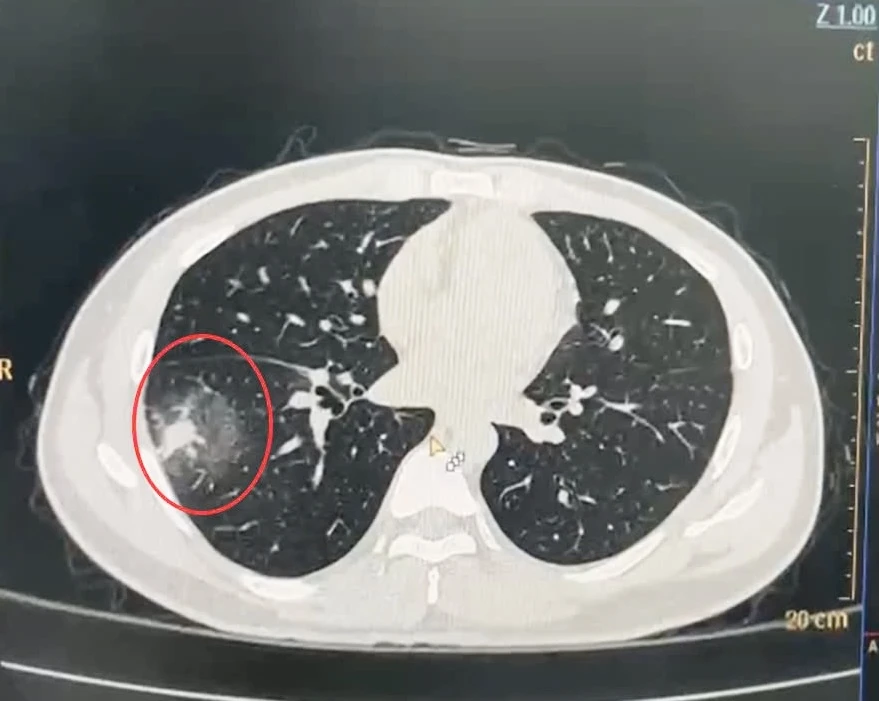

bệnh viêm phổi 0.jpg

Nhu mô phổi của bệnh nhân Q bị tổn thương nặng. Ảnh: TT